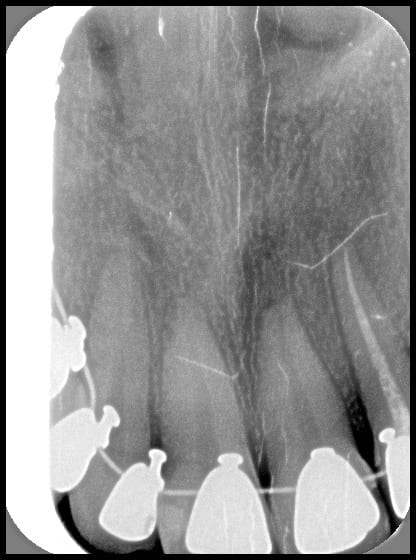

Bjc t'as parlé malheur mon p'tit, je reçois une patiente cet AM même, suivie depuis 6 mois en ODF lingual, regardez moi cette 21....

R sorption hby5uq - Eugenol